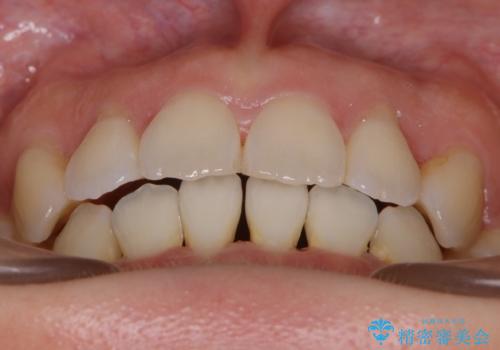

- 前歯のガタつき・噛み合わせの不調を主訴にご来院されました。

患者様のお仕事柄、目立たない装置で矯正したいとのご要望があり、今回はインビザラインを用いて抜歯矯正を行うこととなりました。

本来、抜歯によって得られる大きなスペースのコントロールはワイヤー装置の方が得意とされていますが、こちらの患者様のように犬歯が大きく手前に傾斜していて奥歯の噛み合わせにそれほど問題がないケースではマウスピース装置でも十分にコントロールできることが予測されます。

歯のガタつきの度合いが強い場合や、上下で大きく噛み合わせがズレている時などに、その改善のための大きなスペースを作る代表的手段が「抜歯」です。

一般的には第一小臼歯(犬歯の一つ隣の歯)を抜くことが多く、前歯のガタつきを改善したり口元を引っ込める場合に利用されます。